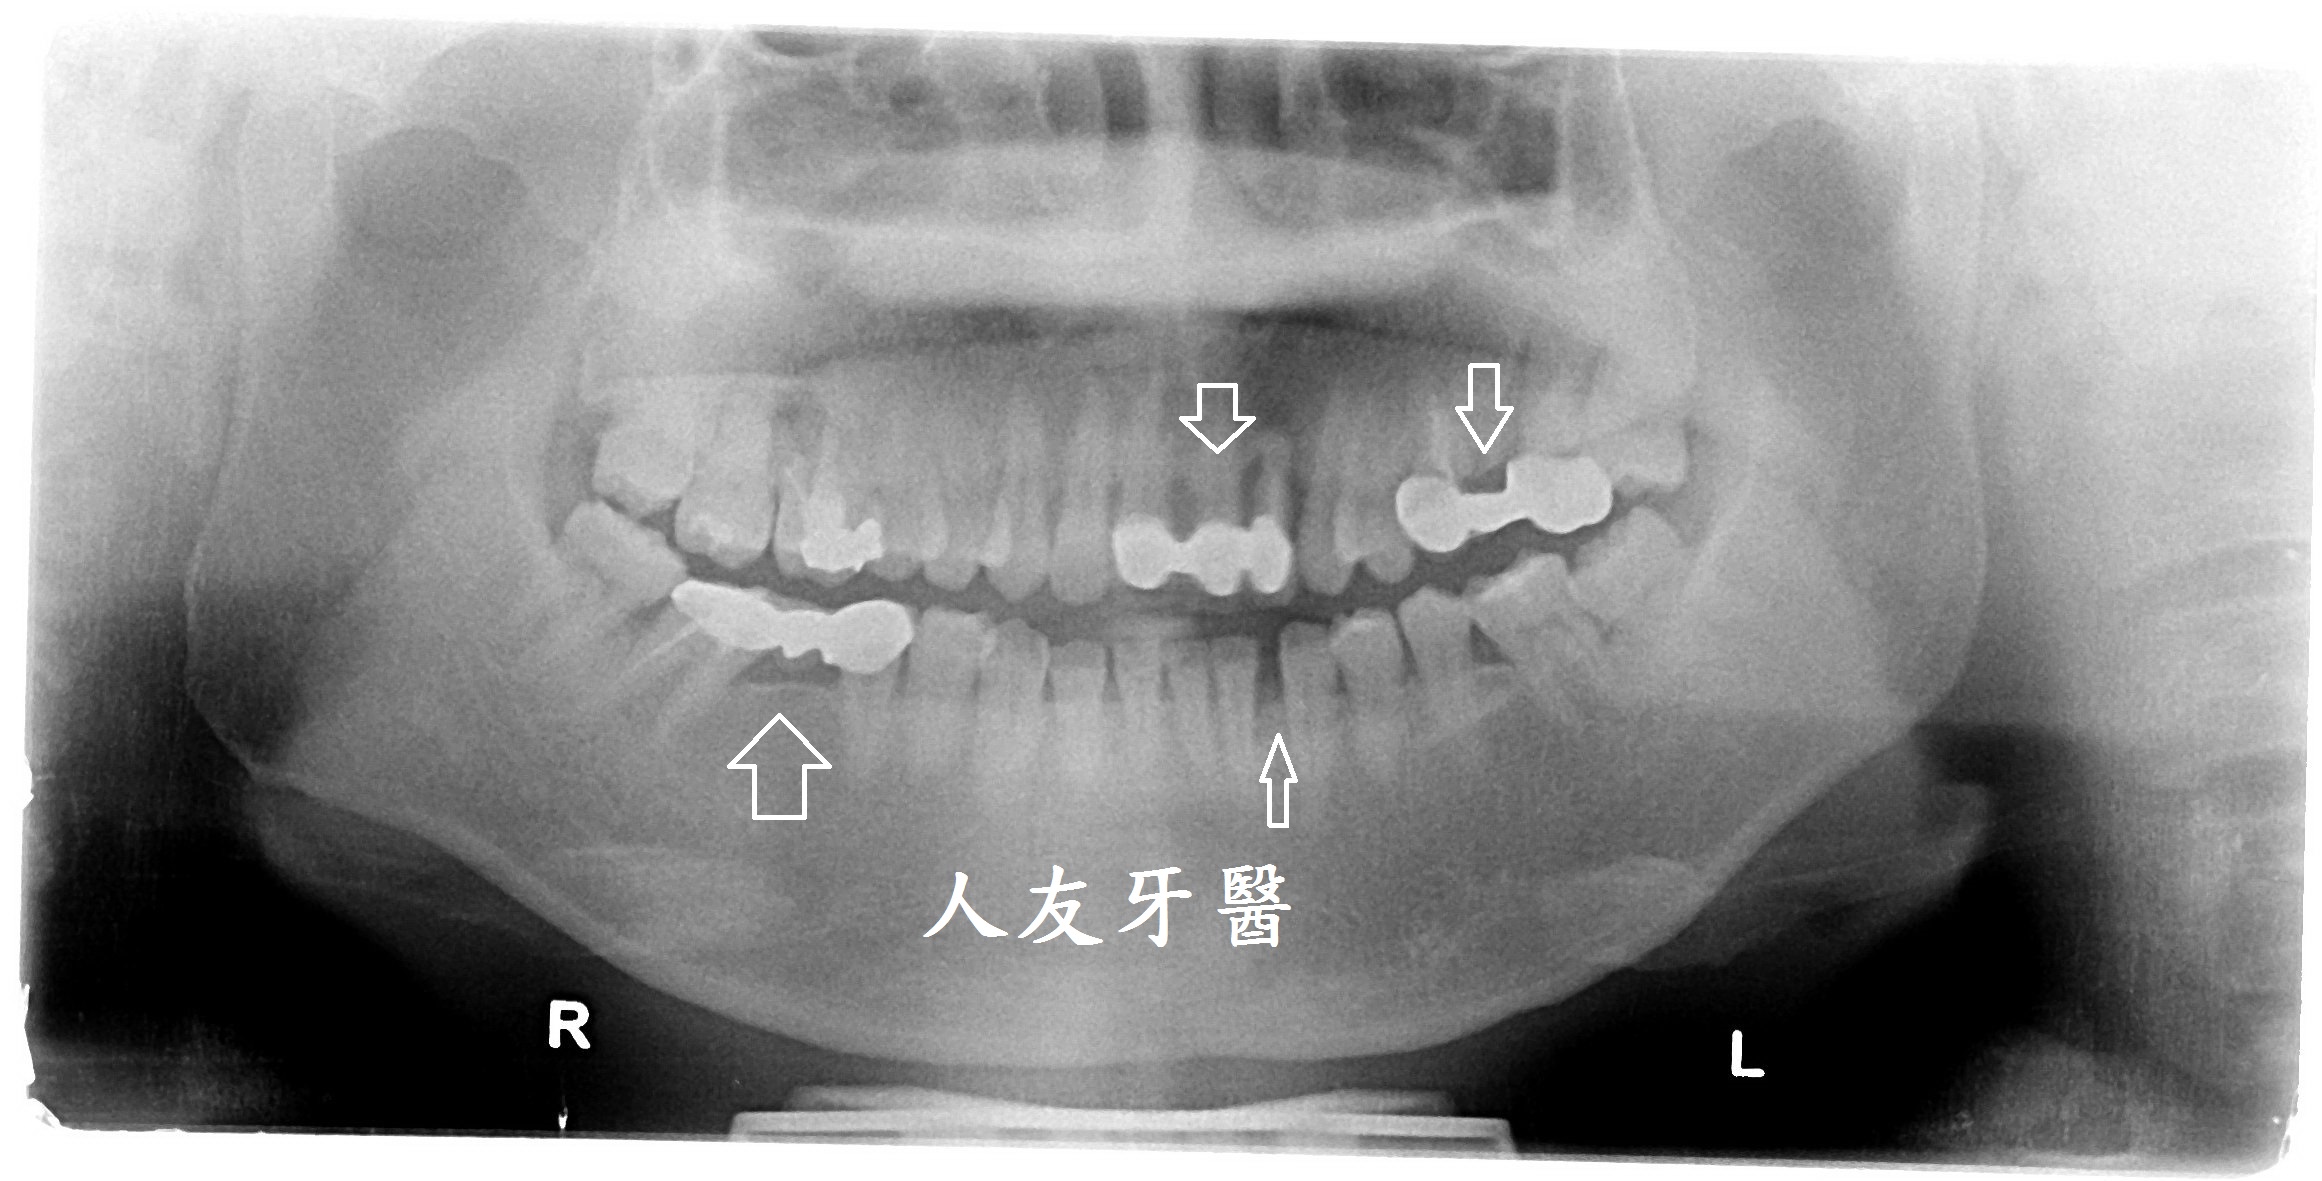

案例分享

有一位26歲女患者訴說她以前洗牙很容易敏感、會痠,但經過本診所進行的舒適型噴粉淨白方式,反而讓她驚訝為什麼不會痛、不會痠,甚至可以改善長期下來愛喝茶、咖啡導致的深層茶垢,這是因為我們使用相較於傳統清潔方式不同地方所在。